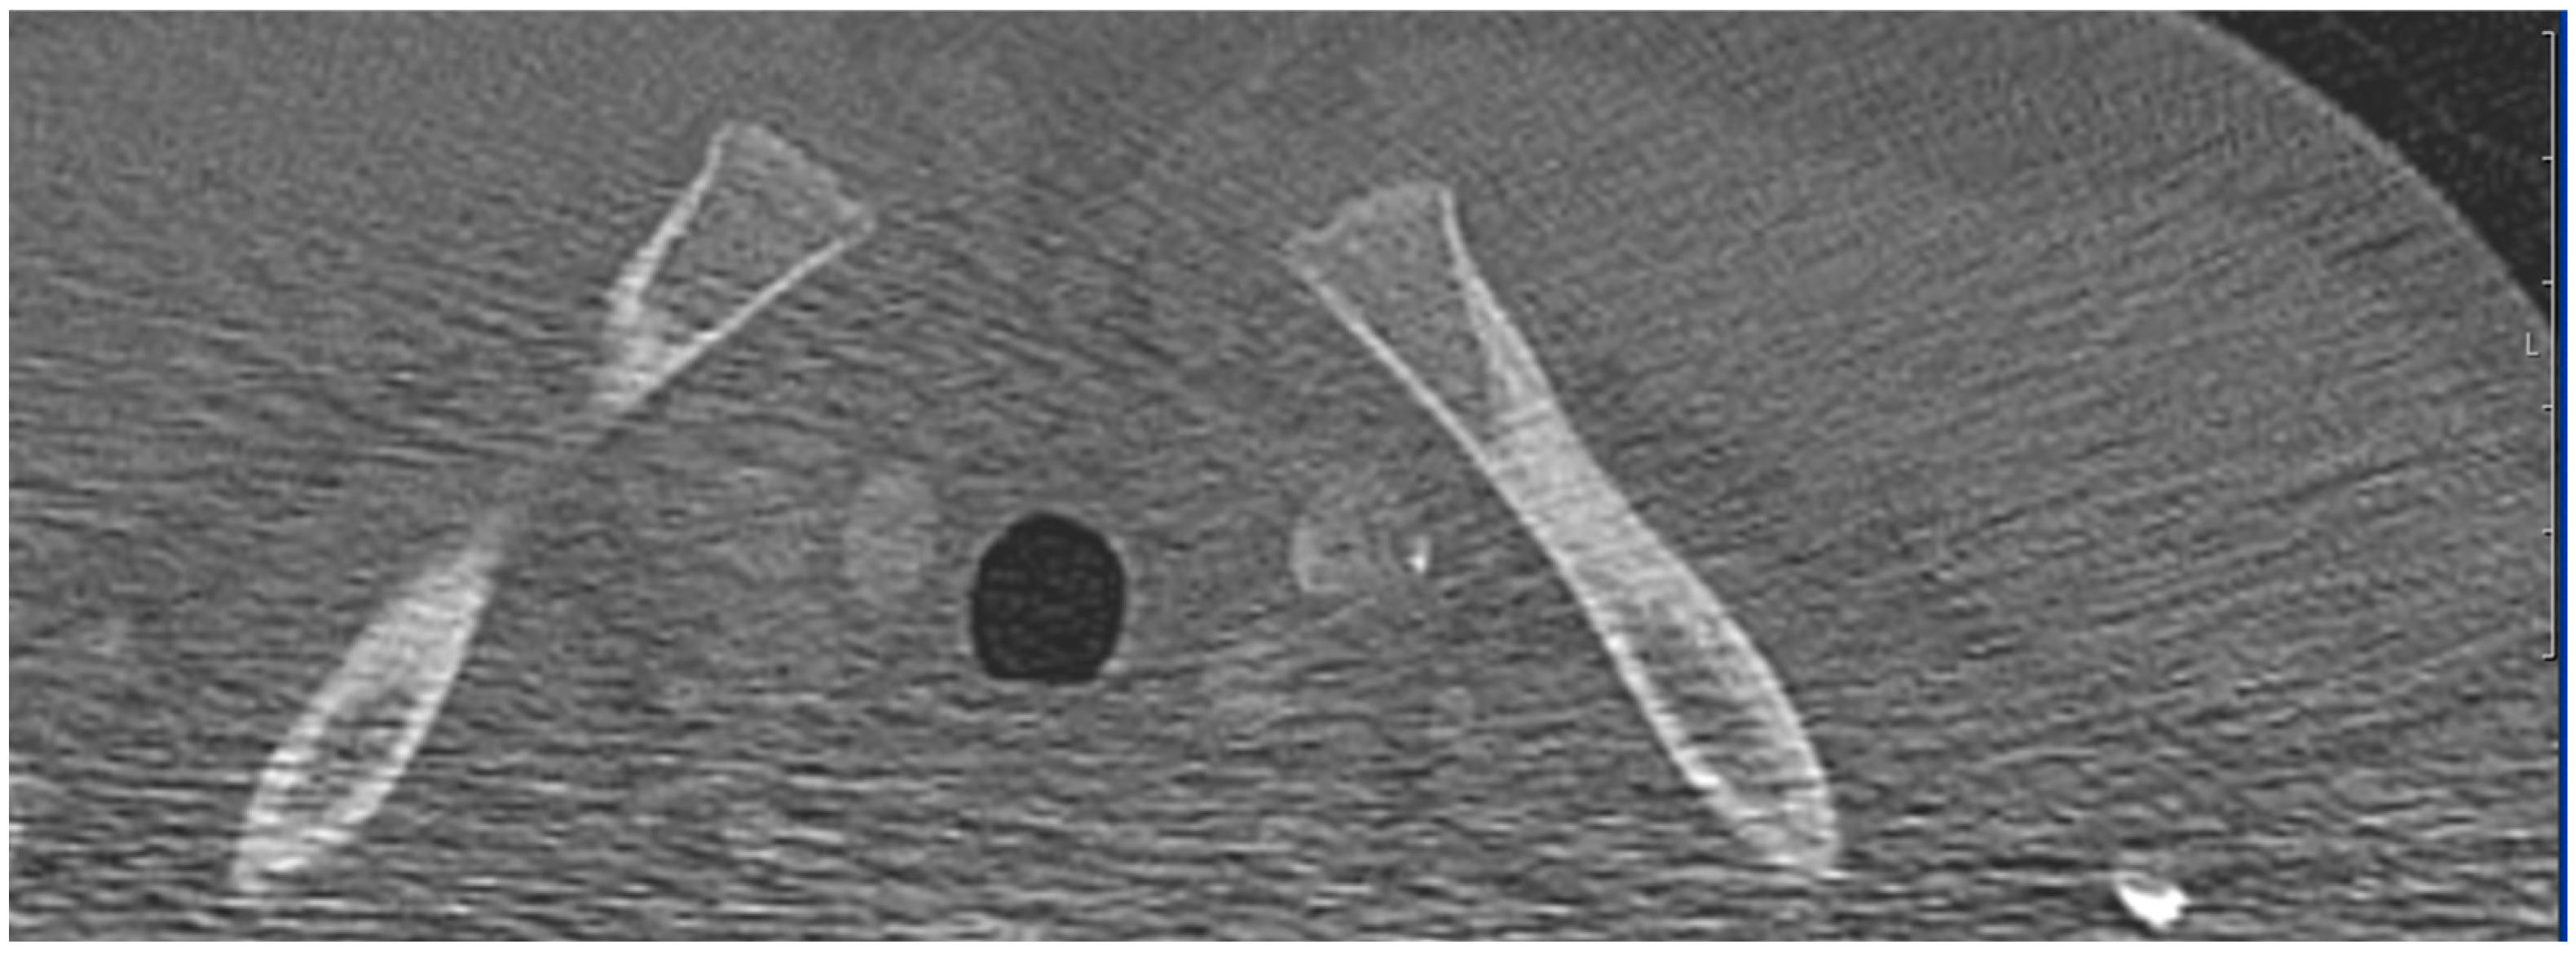

2. Materials and Methods

2.4. Design